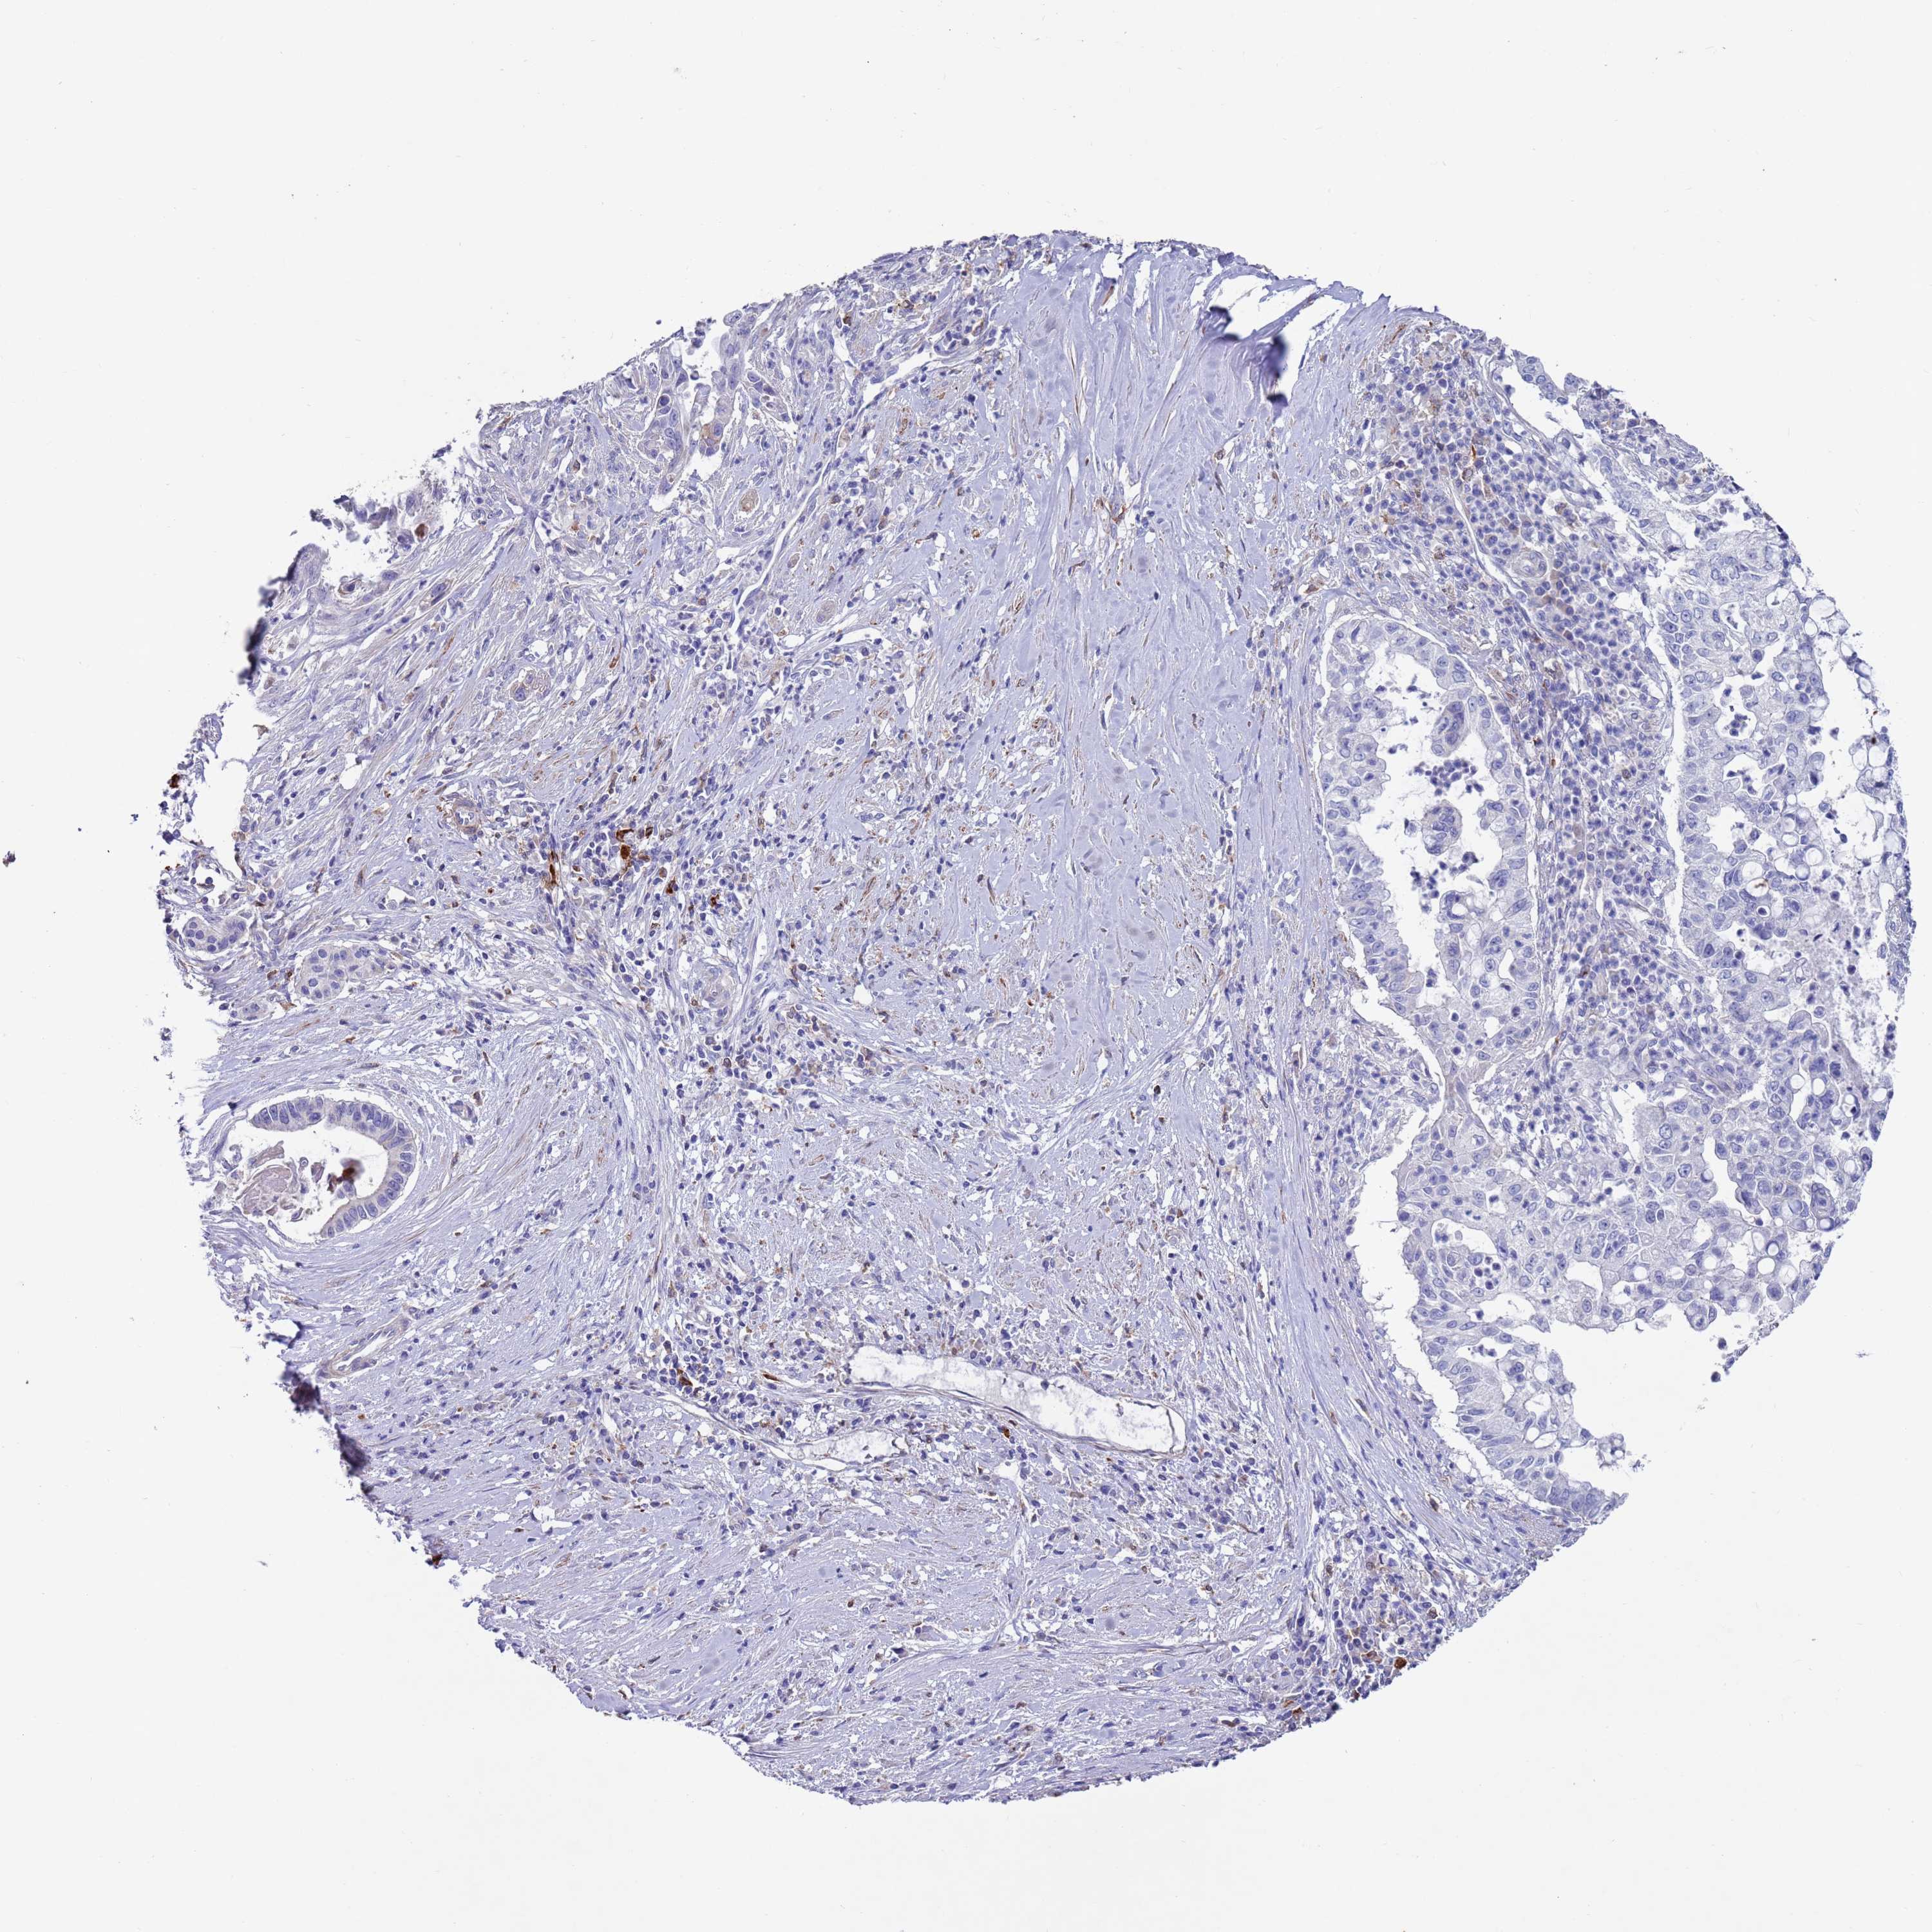

PANCREATIC CANCER - Protein expressioni

A mouse-over function shows sample information and annotation data. Click on an image to view it in a full screen mode. Samples can be filtered based on level of antibody staining by selecting one or several of the following categories: high, medium, low and not detected. The assay and annotation is described here.

Note that samples used for immunohistochemistry by the Human Protein Atlas do not correspond to samples in the TCGA dataset.

Antibody stainingi

Antibody staining in the annotated cell types in the current human tissue is reported as not detected, low, medium, or high, based on conventional immunohistochemistry profiling in selected tissues. This score is based on the combination of the staining intensity and fraction of stained cells.

Each image is clickable and will lead to virtual microscopy that enables deeper exploration of all samples and also displays staining intensity scores, fraction scores and subcellular localization as well as patient and tissue information for each sample.

Antibody HPA041647

Antibody HPA044218

Staining

High

Medium

Low

Not detected

Intensity

Strong

Moderate

Weak

Negative

Quantity

>75%

75%-25%

<25%

None

Location

Nuclear

Cytoplasmic/membranous

Cytoplasmic/membranous,nuclear

Adenocarcinoma, NOS